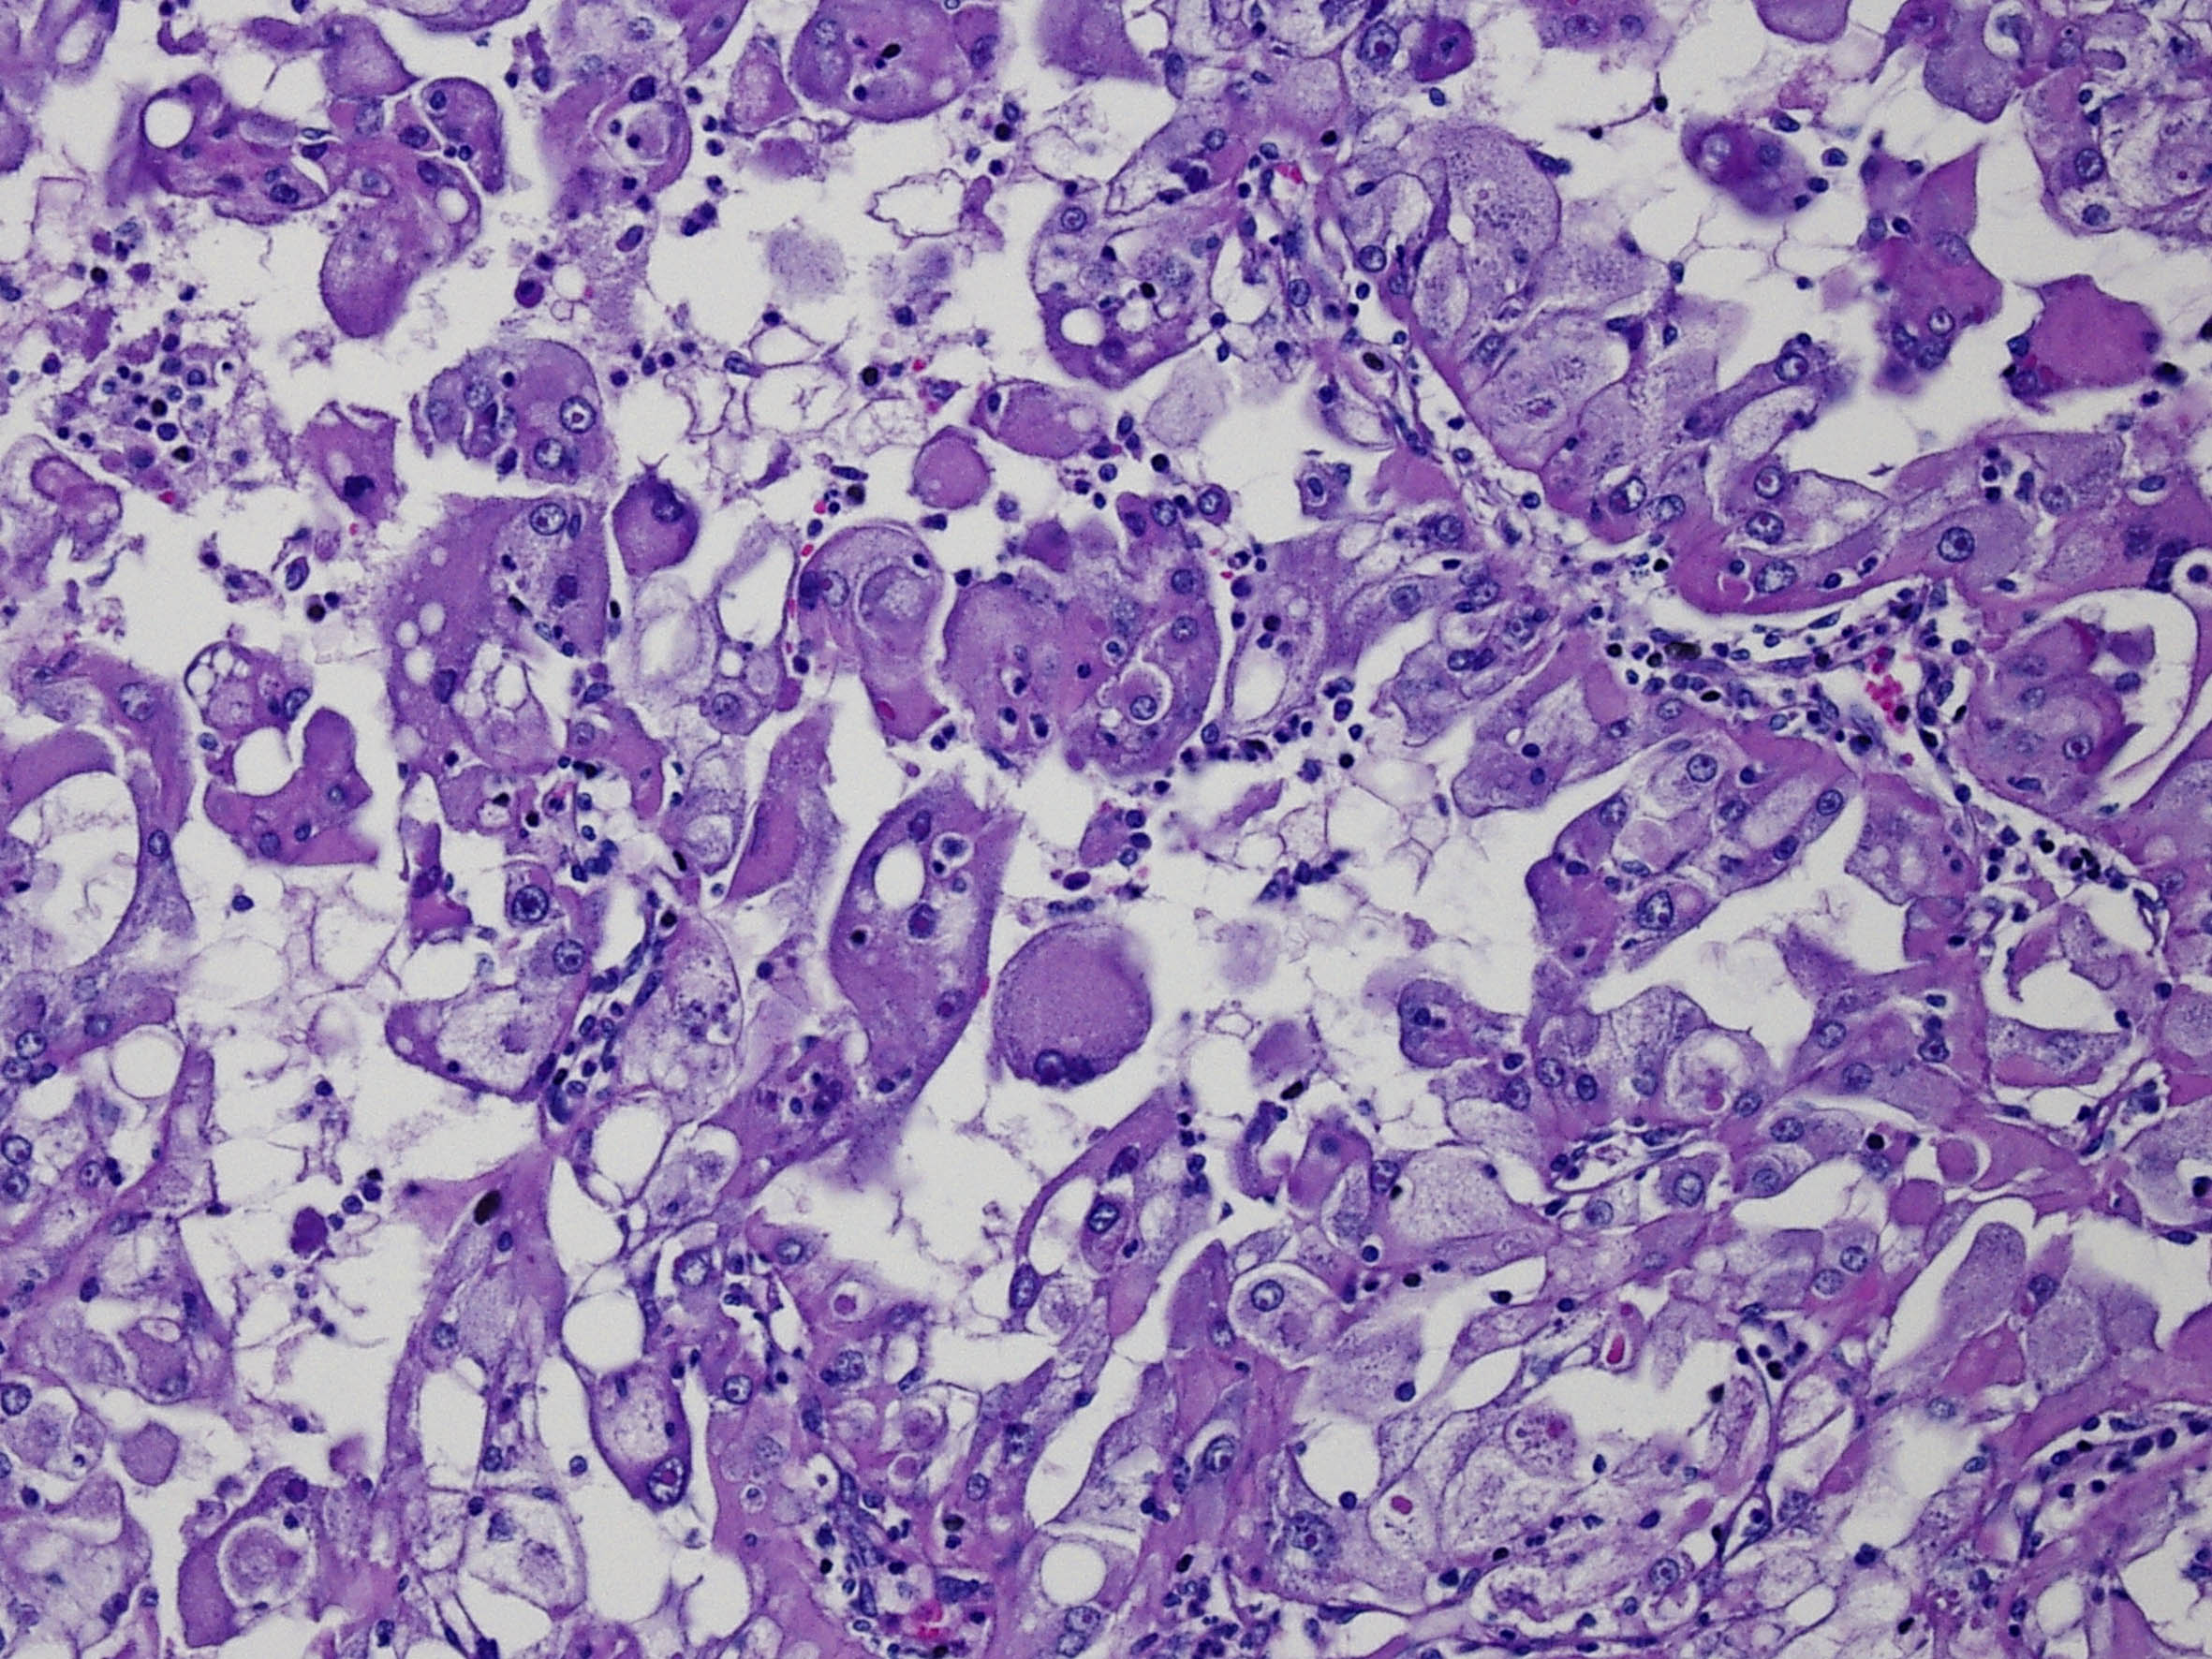

Classification of renal tumors

Case ID: 59